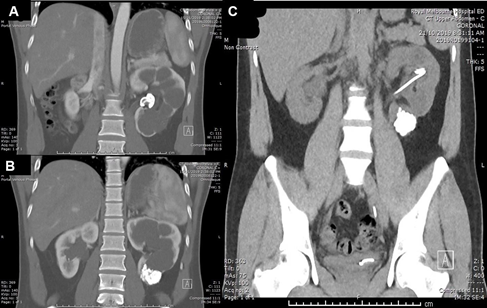

A 26-year-old Nepalese man was referred to the urologists for a large renal pelvic calculus found on an ultrasound done for hypertension workup. His blood pressures were up to 158/116mmHg and he was otherwise asymptomatic. A quadruple-phase computed tomography (CT) showed an obstructive 29mm left renal pelvis calculus, Grade 4 hydronephrosis, and extensive small non-obstructing calculi in the left lower pole with cortical thinning (Figure 1A&1B). The length of the left kidney was preserved at 11cm due to the hydronephrosis, but the renal parenchyma was thin at 6mm, compared to the 10cm-long right kidney with a parenchymal thickness of 11mm. He had preserved renal function with creatinine of 80umol/L. A 99mTc-MAG3 renogram showed reduced uptake and transit in the left lower kidney. There was no tracer drainage after Frusemide injection, with a half-life of 140min (Figure 2A). The differential left renal function was 40%. A retrograde pyelogram performed revealed no ureteric abnormalities. Due to the multiloculated hydronephrotic appearance on CT, renal tuberculosis was considered and ruled out with negative Quantiferon-gold testing. His other medical history includes asthma.

A 99mTc-DMSA was performed, showing irregular parenchymal thinning and scarring, and absent cortical uptake in the left lower kidney (Figure 2B). The left renal function was 44%. A repeat non-contrast CT showed no more renal pelvis stones but still extensive calculi in the dilated lower pole (Figure 1C).

Figure 1 Pre and post RIRS CT images. (A) Initial scan shows left obstructing renal pelvic stone. (B) Initial scan also shows multiple small non-obstructing calculi in lower pole. (C) CT image post second RIRS demonstrate clearance of pelvic stone but residual calculi in lower pole.